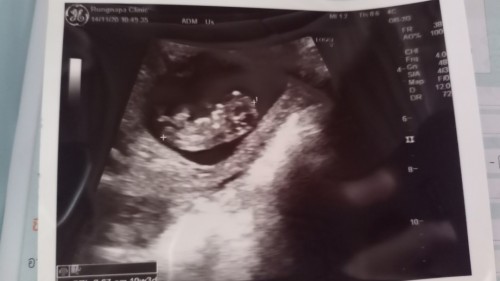

ค่ะ ตอนนี้ไม่รู้ว่าหนูน้อยเพศอะไร แต่ก็จะติดตามคุณแม่ศิวพรรอดูว่าเราจะได้ลูกเพศอะไรกันนะคะ